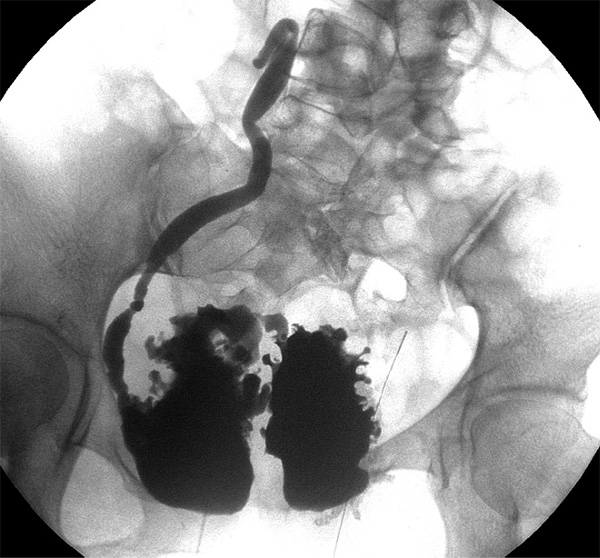

术前膀胱造影

· 影像尿动力显示膀胱安全容量显著增加,返流级别下降,膀胱形态较前明显改善。